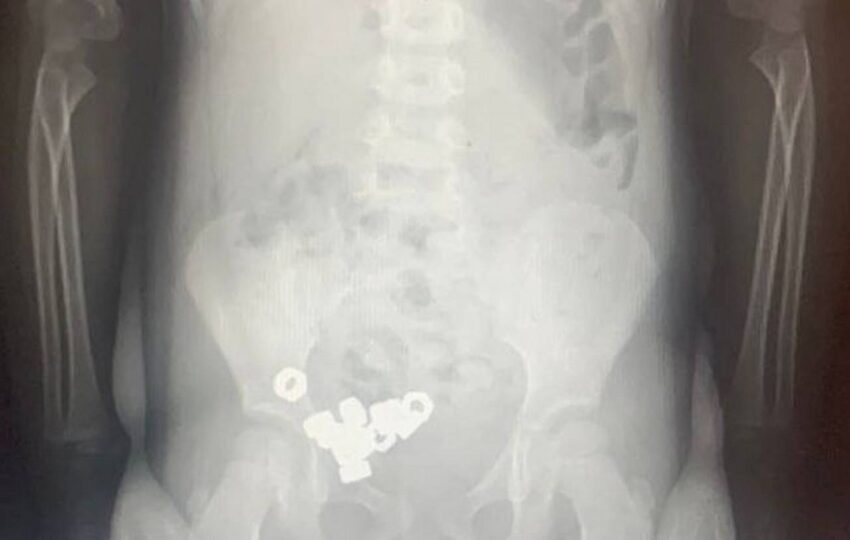

Трёхлетнего мальчика привезли в детское приёмное отделение второй воронежской городской больницы после подозрений родителей, что ребёнок мог случайно съесть посторонние предметы. При осмотре врачи не обнаружили явных признаков патологии, но сделанный рентген брюшной полости показал наличие большого количества тёмных теней (в общей сложности шестнадцати маленьких гаек) в желудочно-кишечном тракте пациента, сообщается в пресс-релизе регионального Минздрава. ...